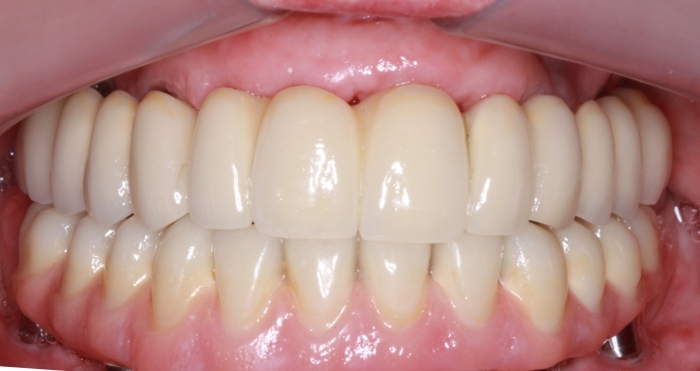

Controle do paciente, em 2016 - Clínica Cliniface

Controle do paciente, em 2016